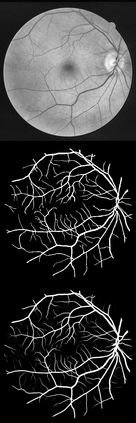

U-Net has been providing state-of-the-art performance in many medical image segmentation problems. Many modifications have been proposed for U-Net, such as attention U-Net, recurrent residual convolutional U-Net (R2-UNet), and U-Net with residual blocks or blocks with dense connections. However, all these modifications have an encoder-decoder structure with skip connections, and the number of paths for information flow is limited. We propose LadderNet in this paper, which can be viewed as a chain of multiple U-Nets. Instead of only one pair of encoder branch and decoder branch in U-Net, a LadderNet has multiple pairs of encoder-decoder branches, and has skip connections between every pair of adjacent decoder and decoder branches in each level. Inspired by the success of ResNet and R2-UNet, we use modified residual blocks where two convolutional layers in one block share the same weights. A LadderNet has more paths for information flow because of skip connections and residual blocks, and can be viewed as an ensemble of Fully Convolutional Networks (FCN). The equivalence to an ensemble of FCNs improves segmentation accuracy, while the shared weights within each residual block reduce parameter number. Semantic segmentation is essential for retinal disease detection. We tested LadderNet on two benchmark datasets for blood vessel segmentation in retinal images, and achieved superior performance over methods in the literature. The implementation is provided \url{https://github.com/juntang-zhuang/LadderNet}